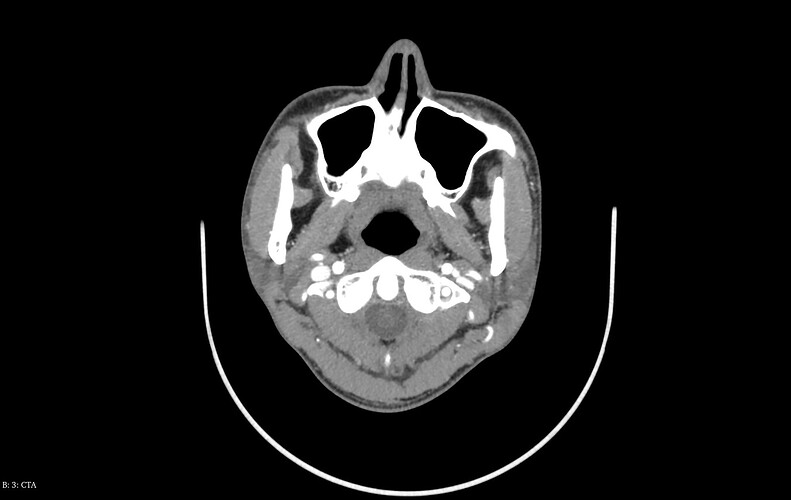

I can’t label images, & I’m going to leave @TML this one to look at, you have alot going on in there! I would guess a flattened IJV on your left, but won’t comment on anything else!

@NoneElongatedStyloid see attached your annotated imaging.

Your left IJV appears to be compressed between your c1 and your styloid. I’mpretty sure your left styloid is the one I have labelled in the top right of the picture, but there is also a white dot between your left ICA and left IJV and I’m not sure what it is. It’s likely another blood vessel or something? Your right side seems pretty okay. That being said, I think your hyoid greater horns are contributing to your symptoms, particularly your right greater horn.

@NoneElongatedStyloid I’m not sure if you saw it, but a week ago I uploaded this annotated image of your greater horns. You can scroll up to see what I had to say about it and why I think it’s causing you problems. I think your right greater horn is worse since it’s touching your right ICA. But I think the left should be removed too.